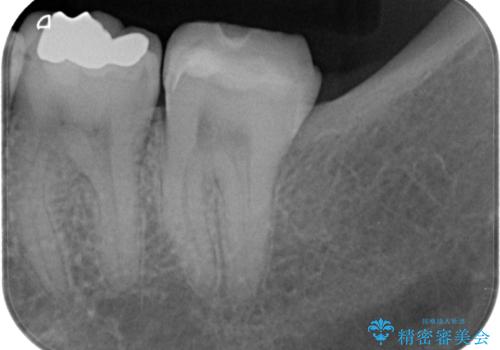

- 詰め物が欠けて虫歯になっていることを気にして来院された患者様です。以前に保険のプラスチックの治療を行われていた状況でした。

歯と歯が接しているところの虫歯のため、セラミックの詰め物(セラミックインレー)での治療を進めていくことにしました。

拡大鏡視野下で、保険のプラスチック、虫歯の除去を行い、セラミックインレーに適した形に整えました。